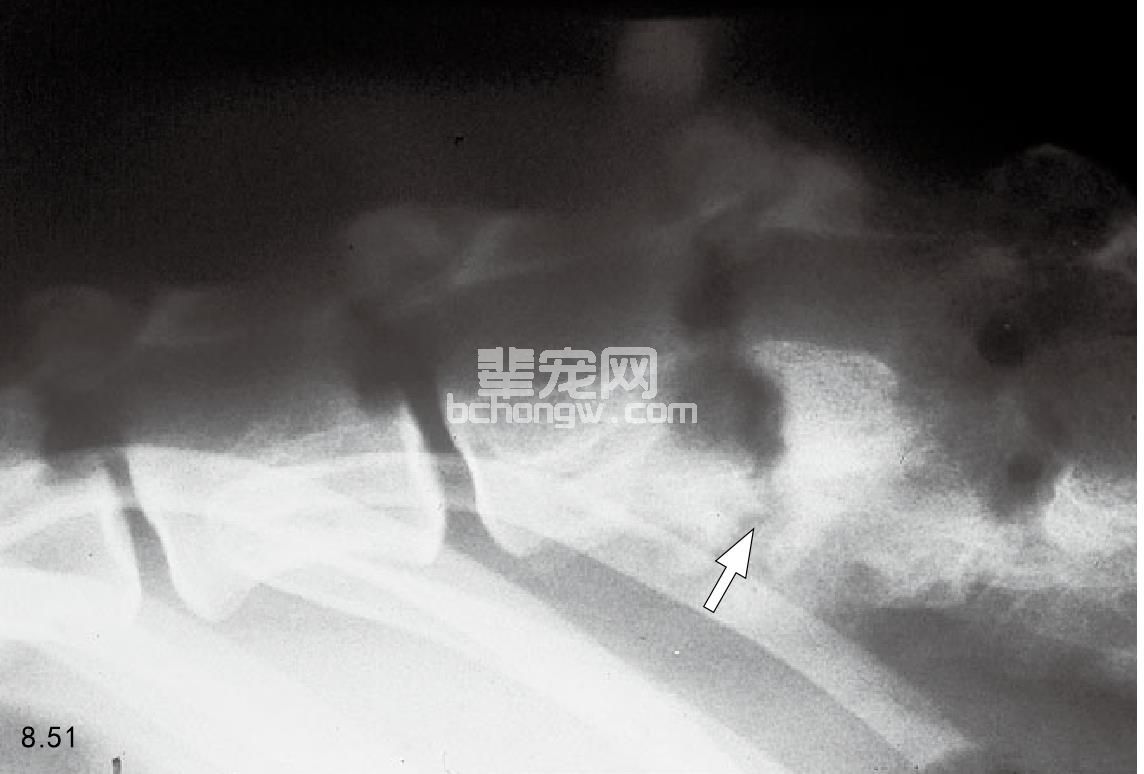

诊断 一般利用X线拍片检查诊断,显示椎骨终板溶解后的椎间盘破裂(图8.51~图8.53),溶解与椎关节 强硬性变形有不同的特征,但是脊髓的肿瘤也有相似的特点。然而,在终板处的椎体肿瘤并不常见,并且很少 涉及到椎骨连接。血象一般正常,尿液培养约有25%的患病动物呈阳性,应进行血清犬布鲁氏菌试验。

图8.51 4岁雄性罗威纳犬的盘性脊椎炎。椎间盘脊椎炎(盘性脊椎炎)起源于椎间盘内或者附近,病变向椎体连接处扩展(箭头所指)。该病首先显 示的是椎体没有了高密度的钙化的皮质边缘,进行性的椎体终板溶解和随后的椎体溶解。